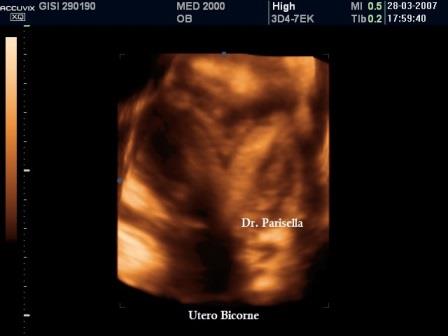

Utero Bicorne

L'utero bicorne è conseguenza della mancata o incompleta fusione dei dotti di Muller e rappresenta circa il 10% di tutte le anomalie mulleriane. E' caratterizzato dalla presenza di due distinti corni uterini divergenti che si fondono verso il fondo dell'utero o a livello del segmento uterino inferiore o a livello dell'istmo ( utero bicorne unicolle).

Dal punto di vista ecografico si osserva una divergenza degli echi endometriali, meglio evidente alla elaborazione 3D. Importante la diagnosi differenziale con l'utero setto (nell'utero bicorne si ha una incisura del fondo uterino maggiore di 10 mm.) e con l'utero didelfo (nell'utero bicorne i due corpi sono separati tra di loro da un angolo superiore a 60°).

Se si associa la presenza di una vagina atresica o di setti vaginali (25% dei casi) possono associarsi anomalie dell'apparato urinario (agenesia renale, rene ipotrofico, ectopia renale).

L'utero bicorne non è causa di infertilità ma sono più frequenti gli aborti spontanei nel I trimestre e soprattutto il parto pretermine, perchè le due cavità uterine sono più piccole.

E' importante sottolineare che anche l'utero bicorne non è incompatibile con il completamento di una gravidanza fisiologica.